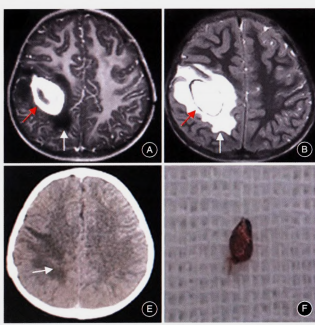

1.小骨窗显微手术:是治疗儿童脑型肺吸虫病的有效方法,具有缩短手术时间,显微镜下顺利寻找病灶边界,减少对周围正常脑组织的牵拉。手术创伤小、恢复周期短,做到对脑组织及周围神经损伤最小。